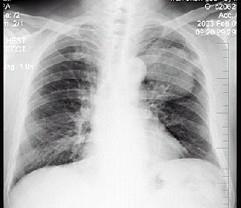

问题 男性,70岁,因胸痛就诊,不咳嗽、发热,X线检查如图,最可能的诊断是 ( )

选项 A、左肺炎性假瘤 B、支气管扩张 C、左侧叶间积液 D、左肺癌 E、左肺结核瘤

答案 D